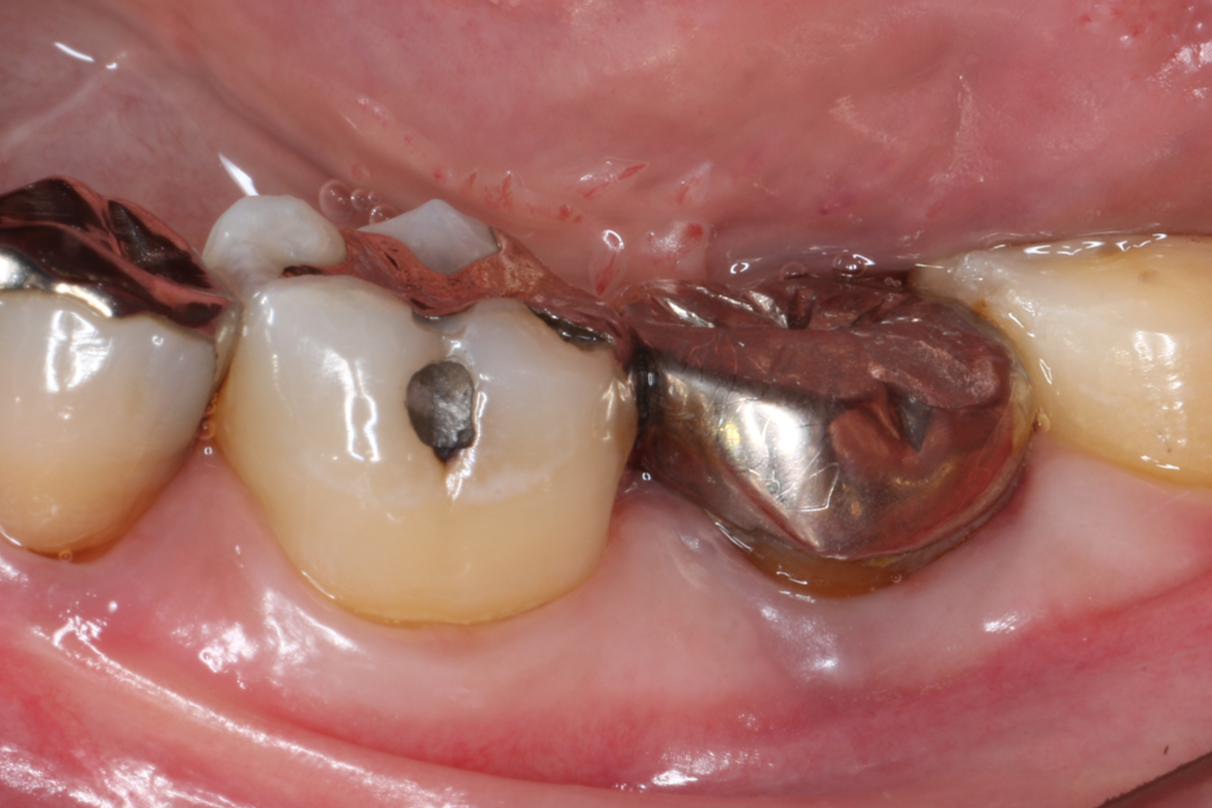

症例1

| 患者様データ | 30代 女性 |

| 来院時の主訴 | 「左下の歯グキが腫れてきた。」 |

| 医院の診断 | 慢性根尖性歯周炎、歯根破折 |

| 治療費 | 総額:425,000円(税抜) 【内訳】 歯牙移植150,000円、精密根管治療80,000円(大臼歯)、ファイバーポストコア20,000円×2、セラミック治療85,000円、ダイレクトボンディング70,000円 |

| リスクと副作用 | ①根管治療歯は長期的には破折するリスク ②長期的なメインテナンスが必要 ③歯根の外部吸収 |

術前に撮影したCT画像から3Dプリンターを用いて親知らずのレプリカを作製することで、 親知らずが乾燥することを防ぎ、成功率が上がるよう努力しています。 |